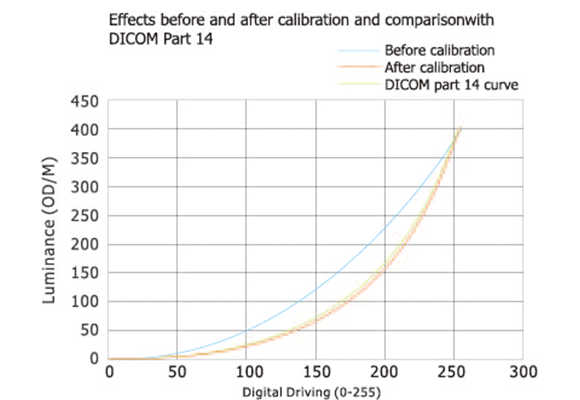

Он прошел строгую калибровку DICOM, может точно отображать медицинские изображения. Встроенный интегрированный датчик подсветки контролирует яркость подсветки, обеспечивая, что дисплей может быстро достигать стабильной яркости при запуске и поддерживать постоянную яркость на протяжении всего жизненного цикла.

Точное отображение медицинских изображений и самых маленьких деталей, поддержание согласованности отображения на разных мониторах, а также согласованности отображения между мониторами и различным оборудованием для визуализации, что обеспечивает точность диагностики.

Встроенный интегрированный датчик подсветки постоянно контролирует яркость подсветки. Он может быстро достичь стабильности яркости при запуске и автоматически компенсировать изменения температуры окружающей среды и потерю яркости, вызванную длительным использованием, поддерживая стабильность яркости на протяжении всего жизненного цикла продукта.